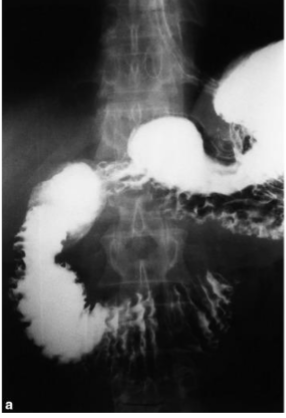

What is this and what type of scan

Crohns, Upper GI w sm bowel follow through